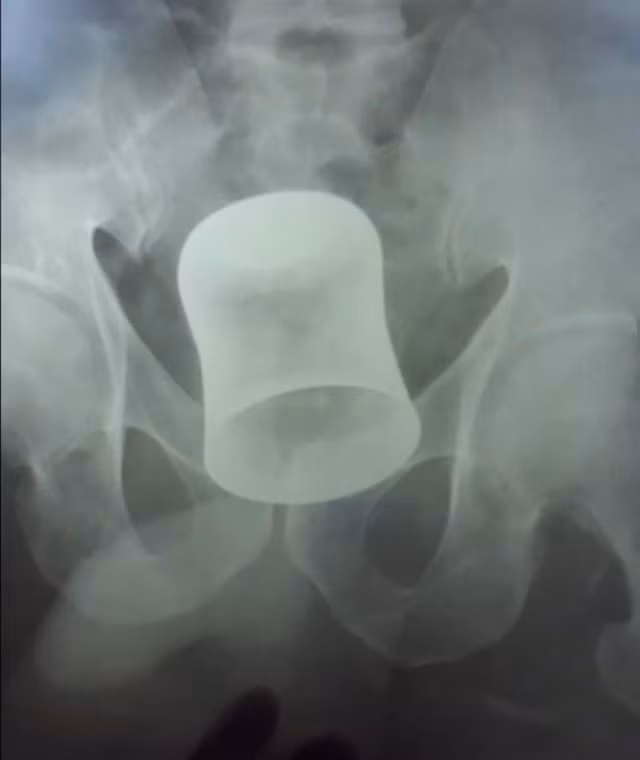

Mười ngày sau, Ramdin đến bệnh viện và một lần chụp chiếu cho thấy ông có một cái cốc bằng thép nằm bên trong cơ thể. Các bác sĩ tại bệnh viện Rama thuộc thành phố Kanpur, bang Uttar Pradesh, Ấn Độ đã phải phẫu thuật hậu môn của ông để lấy chiếc cốc ra ngoài.

Cụ thể là sau 10 ngày, vào ngày 26/6, ông ta đã bị đau bụng dữ dội. Chúng tôi đã tiến hành siêu âm để tìm ra vấn đề và ngạc nhiên khi thấy một cái cốc bằng thép nằm bên trong bụng bệnh nhân. Có vẻ như chiếc cốc kim loại được đưa vào trực tràng của Ramdin bởi những kẻ bất lương và nó mắc kẹt gần ruột, khiến ông ấy đau đớn dữ dội.